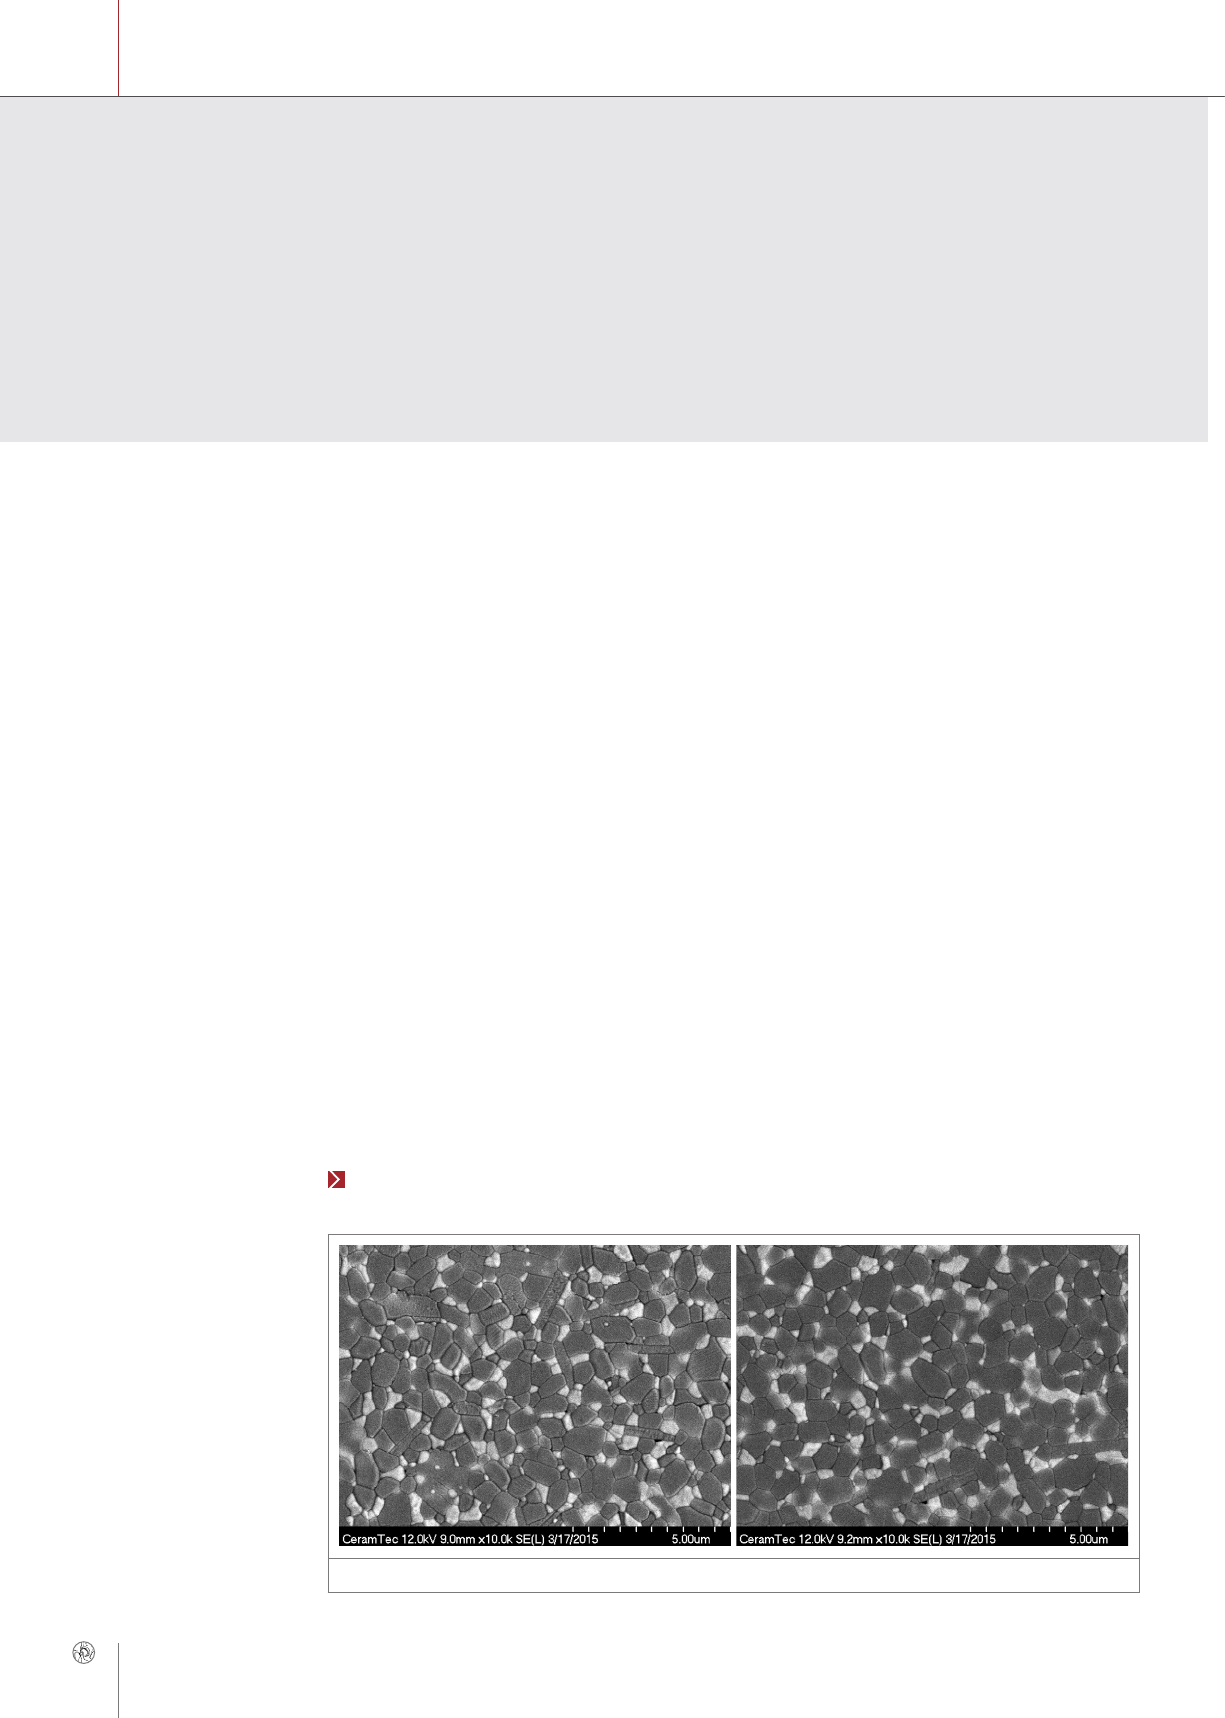

Figure 2: CoC bearings for hip arthroplasty

cant ( Fig. 1).

Conclusions

In summary, the only bearing-related complications

reported by the patients included in the DESIT study

at about 4 years' mean follow-up are transient nois-

es. Bearing diameter larger than 28 mm was shown

to improve patients’ satisfaction with their hip re-

placements, while absence of osteolysis and of ce-

ramic fractures confirms the excellent mechanical

and wear behavior of CoC bearings ( Fig. 2). ■